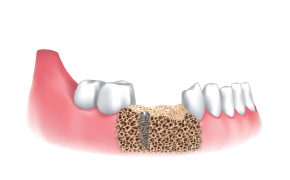

El hueso obtenido se observa con facilidad a través de la pantalla de silicona transparente.

El hueso se transfirió a un frasco luego de desensamblar la pantalla de silicona y stopper.

La cantidad de hueso fue mucho más que la esperada.

Luego de la instalación del implante, se conectan los pilares de cicatrización y se lleva a cabo la regeneración ósea en el defecto.